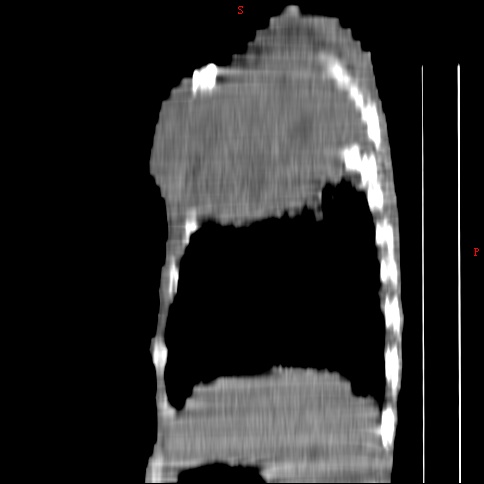

患者男,81岁,咳喘10余年,继往结核病史,发现胸部体表肿物(具体时间不详)就诊

右侧胸廓塌陷。右前上外侧胸壁软组织肿块,其内见有低密度影,肋骨呈溶骨性表现。右肺上叶见大量的间质纤维化表现。右侧膈肌上抬。

患者男,81岁,咳喘10余年,继往结核病史,发现胸部体表肿物

考虑:1、继发性结核,右结核性胸膜炎伴胸壁结核性感染

2、右侧胸壁恶性肿瘤。

肺尖巨大肿块影阴,胸壁受侵肋骨破坏,肿块密度不均且穿破胸壁入皮下,应该是:肺上沟癌;由于肺内有斑片状播散病灶,因此不排除胸壁结核。

患者男,81岁,咳喘10余年,继往结核病史,发现胸部体表肿物。

考虑:1 右侧胸壁恶性肿瘤(多考虑:胸膜间皮瘤)。

2 继发性结核,右结核性胸膜炎伴胸壁结核性感染。